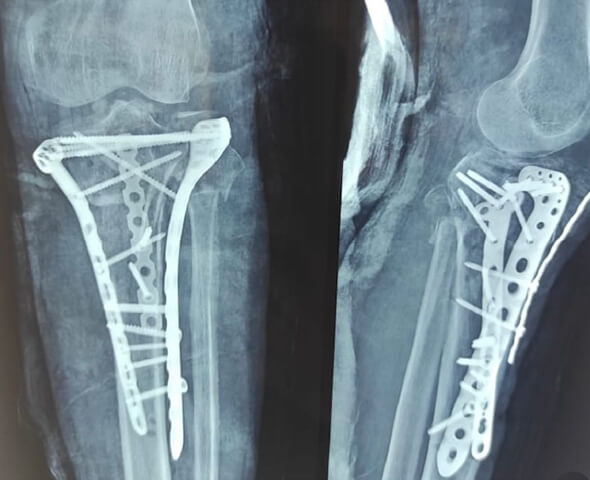

DEFORMITY CORRECTION

TRAUMA